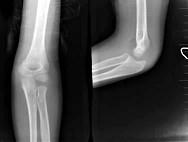

问题 8岁男孩,外伤后感左肘关节肿痛,行左肘关节正侧位摄片如图所示,最可能的诊断是?(?)

选项 A.左肱骨髁上骨折 B.左肱骨小头骨骺I度分离 C.左肱骨髁上细微骨折 D.软组织挫伤 E.以上均不正确

答案 C